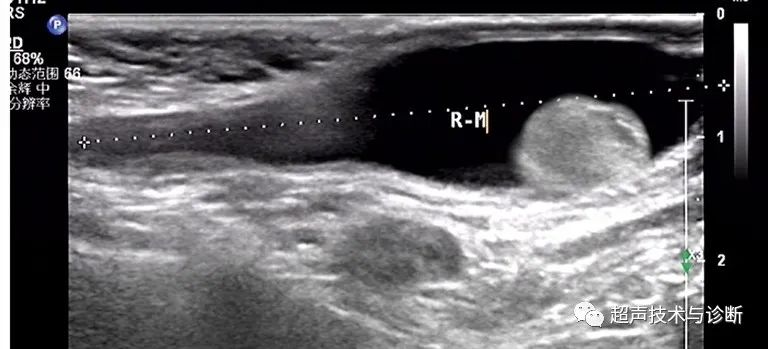

③睾丸精索鞘膜积液——鞘状突内环闭合、精索处及睾丸端未闭合:又称之为婴儿型鞘膜积液,积液与睾丸鞘膜腔相通,而与腹腔不相通。如果积液沿精索向腹股沟区延伸,那可能就成了另一种类型,即睾丸精索鞘膜积液,也就是婴儿型鞘膜积液(如图2所示)。该类型的整体表现类似「茶壶」。

图2示意图显示睾丸-精索鞘膜积液

超声表现为:积液包绕睾丸并向腹股沟区延伸至精索部位,但未与腹腔沟通。

睾丸精索鞘膜积液:积液同时位于位于睾丸及精索鞘膜腔内,位于腹腔沟通